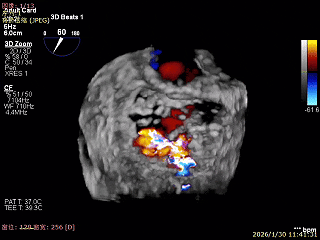

3D Enface 可见反流由2区3区从前后冲出

3D Enface上彩可见夹子内侧无反流,残余外侧反流

3D Enface下组织桥稳定无反流

夹子释放后,反流基本消失